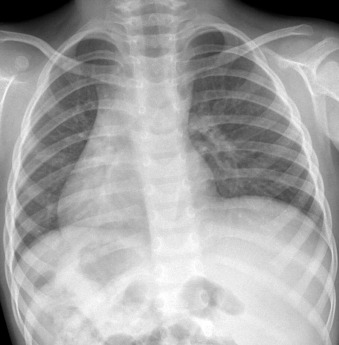

Situs inversus: right apex and right-sided stomach ( Fig. 20-7 )